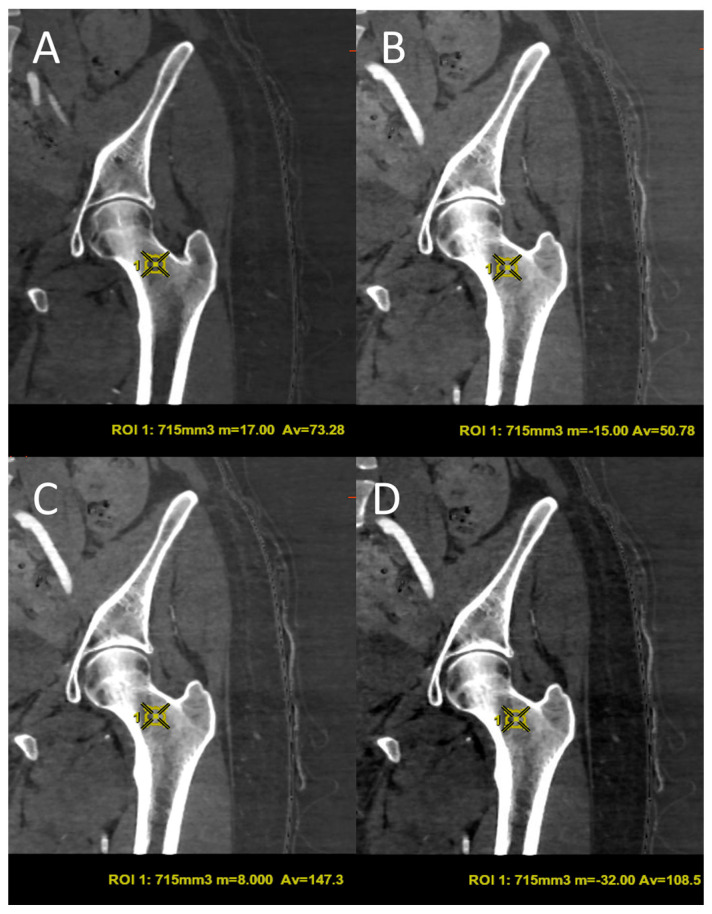

骨矿物质密度(BMD)的评估对骨质疏松症的诊断至关重要。双能x线吸收仪(DXA)是目前的金标准,但它在评估小梁骨方面有局限性,并且容易受到不同的伪影的影响。在这项研究中,我们评估了双能计算机断层扫描(DECT)是否可以作为一种替代方法来评估绝经后接受肿瘤随访的患者的骨密度。本研究对41例6个月内同时行DECT和DXA的患者进行回顾性分析。使用五种不同的基础材料对(BMPs)从DECT中提取骨密度值,并与股骨颈的DXA测量值进行比较。钙-脂肪配对与dxa衍生的骨密度相关性最强(Spearman ρ = 0.797),重复性好(ICC = 0.983)。DXA结果与各种BPM测量之间存在强烈而重要的关联。这些发现支持了当使用特定的BMPs时,DECT在精确和机会性评估BMD变化方面的可能性。这项研究表明,这项技术如何成为传统DXA的有用和有效的替代品,特别是当患者在使用DECT进行肿瘤随访时,最大限度地减少了额外的辐射暴露。

The assessment of bone mineral density (BMD) is essential for osteoporosis diagnosis. Dual-energy X-ray Absorptiometry (DXA) is the current gold standard, but it has limitations in evaluating trabecular bone and is susceptible to different artifacts. In this study we evaluate whether Dual-Energy Computed Tomography (DECT) can be defined as an alternative method for the assessment of BMD in a sample of postmenopausal patients undergoing oncological follow-up. In this study a retrospective analysis was conducted on 41 patients who had both DECT and DXA within six months. BMD values were extracted from DECT using five different base material pairs (BMPs) and compared with DXA measurements at the femoral neck. The calcium-fat pairing showed the strongest correlation with DXA-derived BMD (Spearman's ρ = 0.797) and excellent reproducibility (ICC = 0.983). There was a strong and significant association between the DXA results and the various BPM measurements. These findings support the possibility of DECT in the precise and opportunistic evaluation of BMD changes when employing particular BMPs. This study showed how this technique can be a useful and effective substitute for conventional DXA, particularly when patients are in oncological follow-up using DECT, minimizing additional radiation exposure.